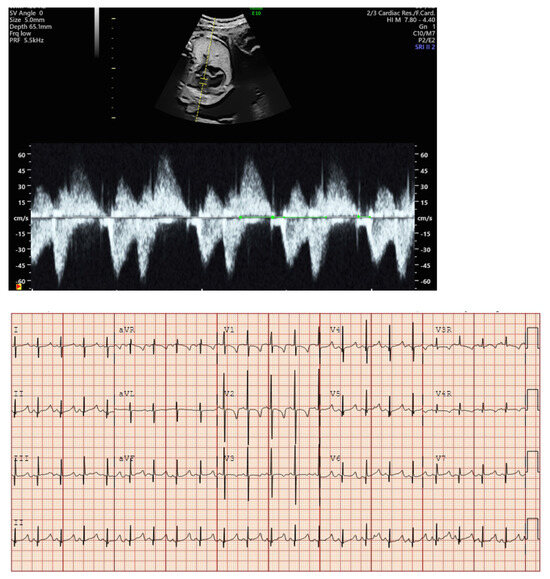

- Atrial flutter (AF) due to a macro-re-entrant pathway within the atrial myocardium and associated with varying degrees of AV block (Figure 2).

| Variable degrees of AV block (primarily 2:1 or 3:1); fixed ventricular rate |